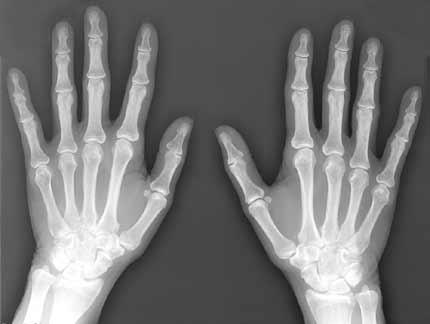

Cần Phân Biệt X-RAYS, CT SCAN, MRI, PET S. - Các phương pháp chụp hình để chẩn bệnh

1. X-rays (X-quang ) là gì? Để hiểu X-quang là gì, trước hết hãy tìm hiểu khái niệm về “sóng điện từ trường” (electromagnetic wave, electromagnetic radiation). Chung quanh chúng ta luôn luôn hiện hữu...